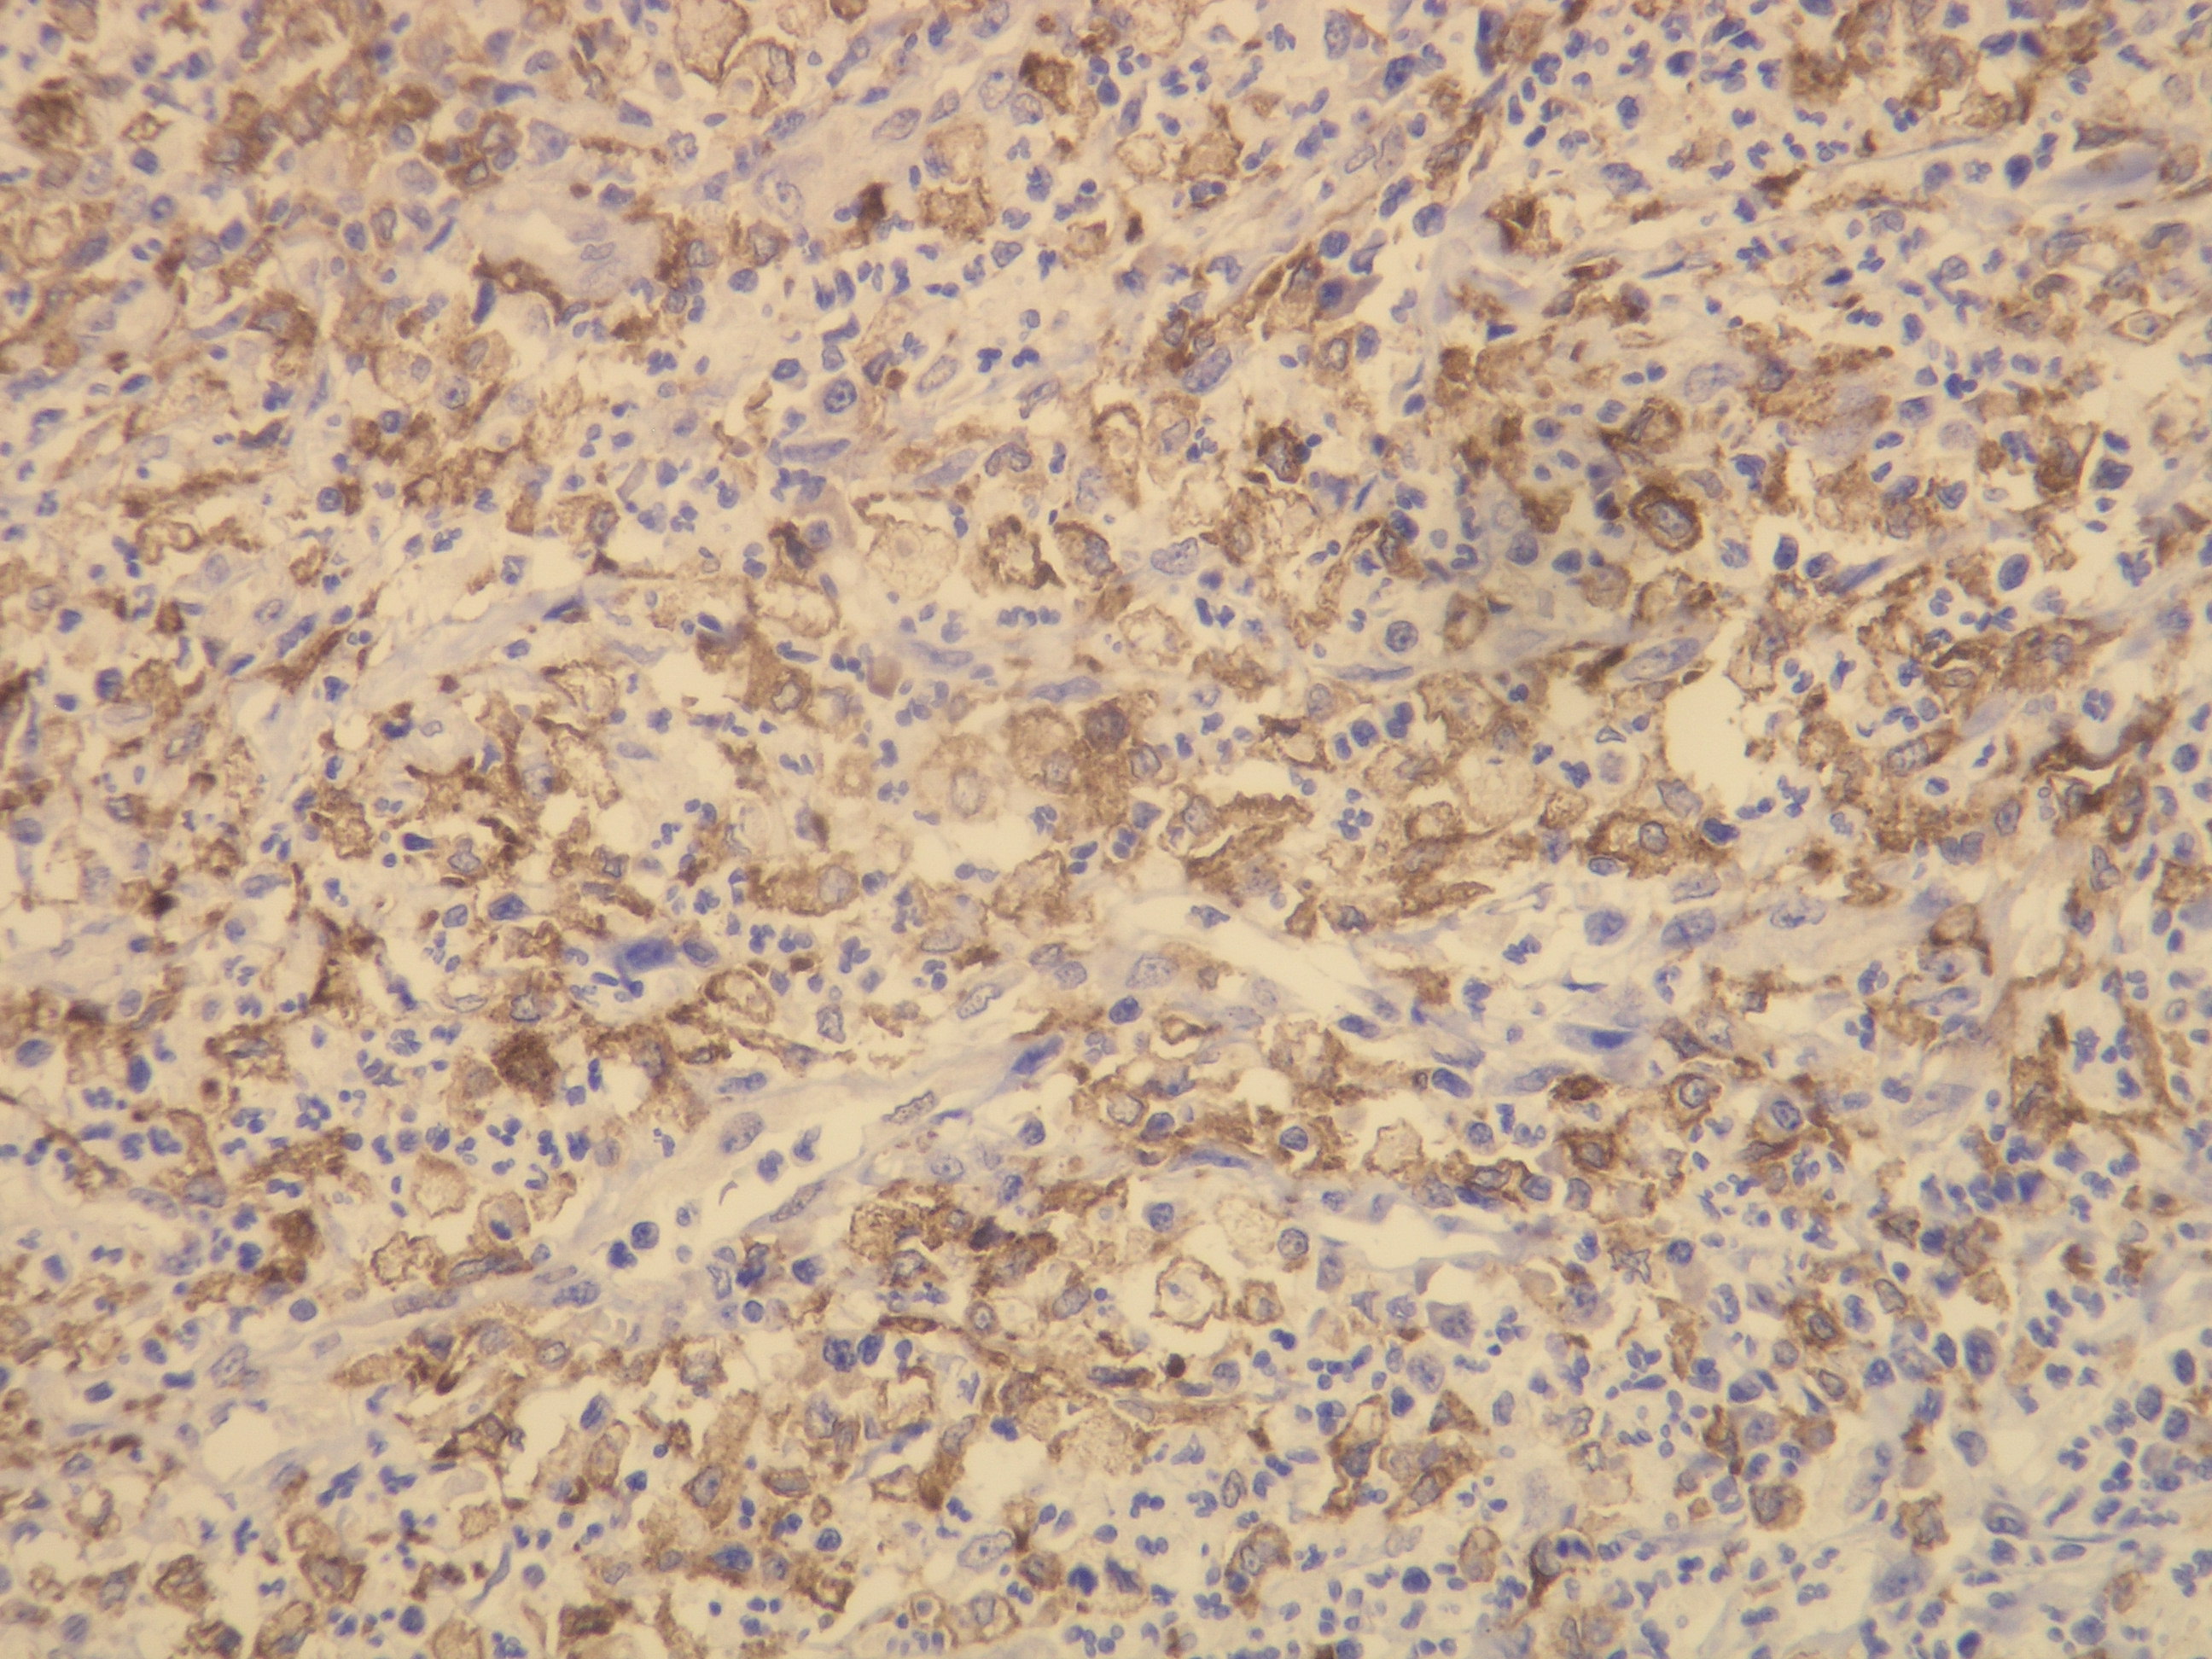

Anti-CD163

Kód produktu:DB 045 Kategória:IHC-P

Peptid derivovaný z N-koncovej sekvencie ľudskej CD163. Protilátka rozpoznáva epitop umiestnený medzi Gly134 - Gly148.

Aplikácia

IHC-P, riedenie 1:100

db045 db045b db045c